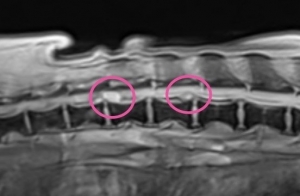

MEDIC矢狀切面(多回波數據採集特殊序列):利用此特殊成像序列,可以觀察到脊髓內可能的出血變化,並且清楚描繪突出的椎間盤邊界與位置,對於手術規劃至關重要。